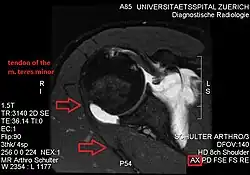

Conjoint and intact tendon disc of teres minor and infraspinatus muscle

Intact teres minor tendon with physiologically hypointense signal

Ultrasonography is a tool to detect a fatty degenerative atrophy of the teres minor and shows in affected muscles increased echogenicity and betimes a slight reduction in muscle bulk. MR imaging helps to consolidate the diagnosis of neurogenic muscle atrophy. Extracellular edema after traumatic events causing neural damage show an increased signal intensity on T2-weighted MRI sequences and normal intensity on T1-weighted sequences. Posterior humeral circumflex artery compression and reduced blood flow in stressful arm positions and or maneuvers can be diagnosed by a Doppler ultrasonography. The nerve should be detected adjacent to the vessel. In an elevated arm position the axillary neurovascular bundle can be seen at the posterior axillary fold just before it perforates the deltoideus, while the posterior course is well visible in the neutral position. For a detailed assessment of the artery, a MR angiography is required. The major task of an ultrasonographic examination is to rule out any space occupying mass. Additional electromyography is helpful to reveal any decelerated nerve conduction velocity, and thus denervation of the concerned muscle.[5]